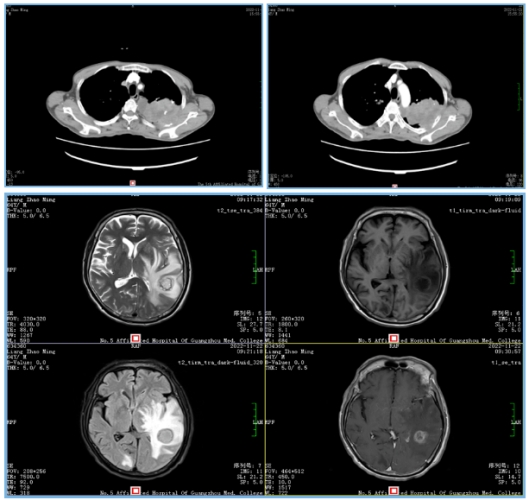

石主任通过多年临床肿瘤治疗经验,综合研判梁叔可能是原发肺部肿瘤转移至脑袋,建议首先完善胸部CT,同时完善头颅增强MR,果不其然,患者胸部CT提示左肺巨大占位约(约200px大小),考虑肺癌可能性大,头颅增强MR提示左侧顶颞叶(62.5px)及右侧枕叶(12.5px)占位,伴大片水肿;临床诊断为肺癌脑转移。

这个时候,聂豪主治医师立马给患者完善肺部肿物穿刺活检,病理提示肺腺癌,这下梁叔病情真相大白,原来就是肺腺癌脑转移,也是目前发病率以及死亡率最高的恶性肿瘤,既往认为出现脑转移,整体生存率只有3到6个月不等。